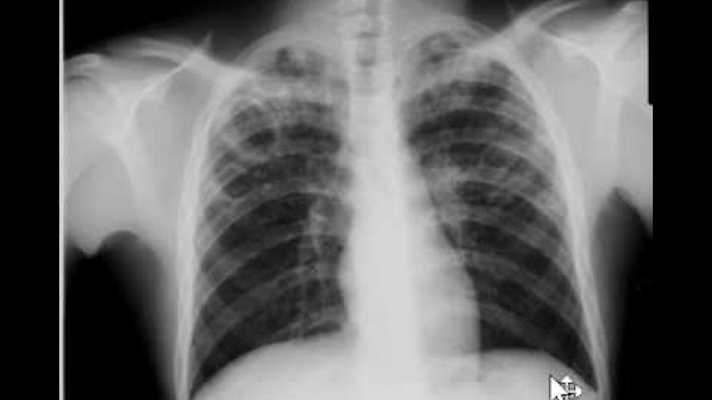

Researchers are training artificial intelligence to identify tuberculosis on chest X-rays, an initiative that could help screening and evaluation efforts in TB-prevalent areas lacking access to radiologists. The findings are part of a study published online in the journal Radiology.